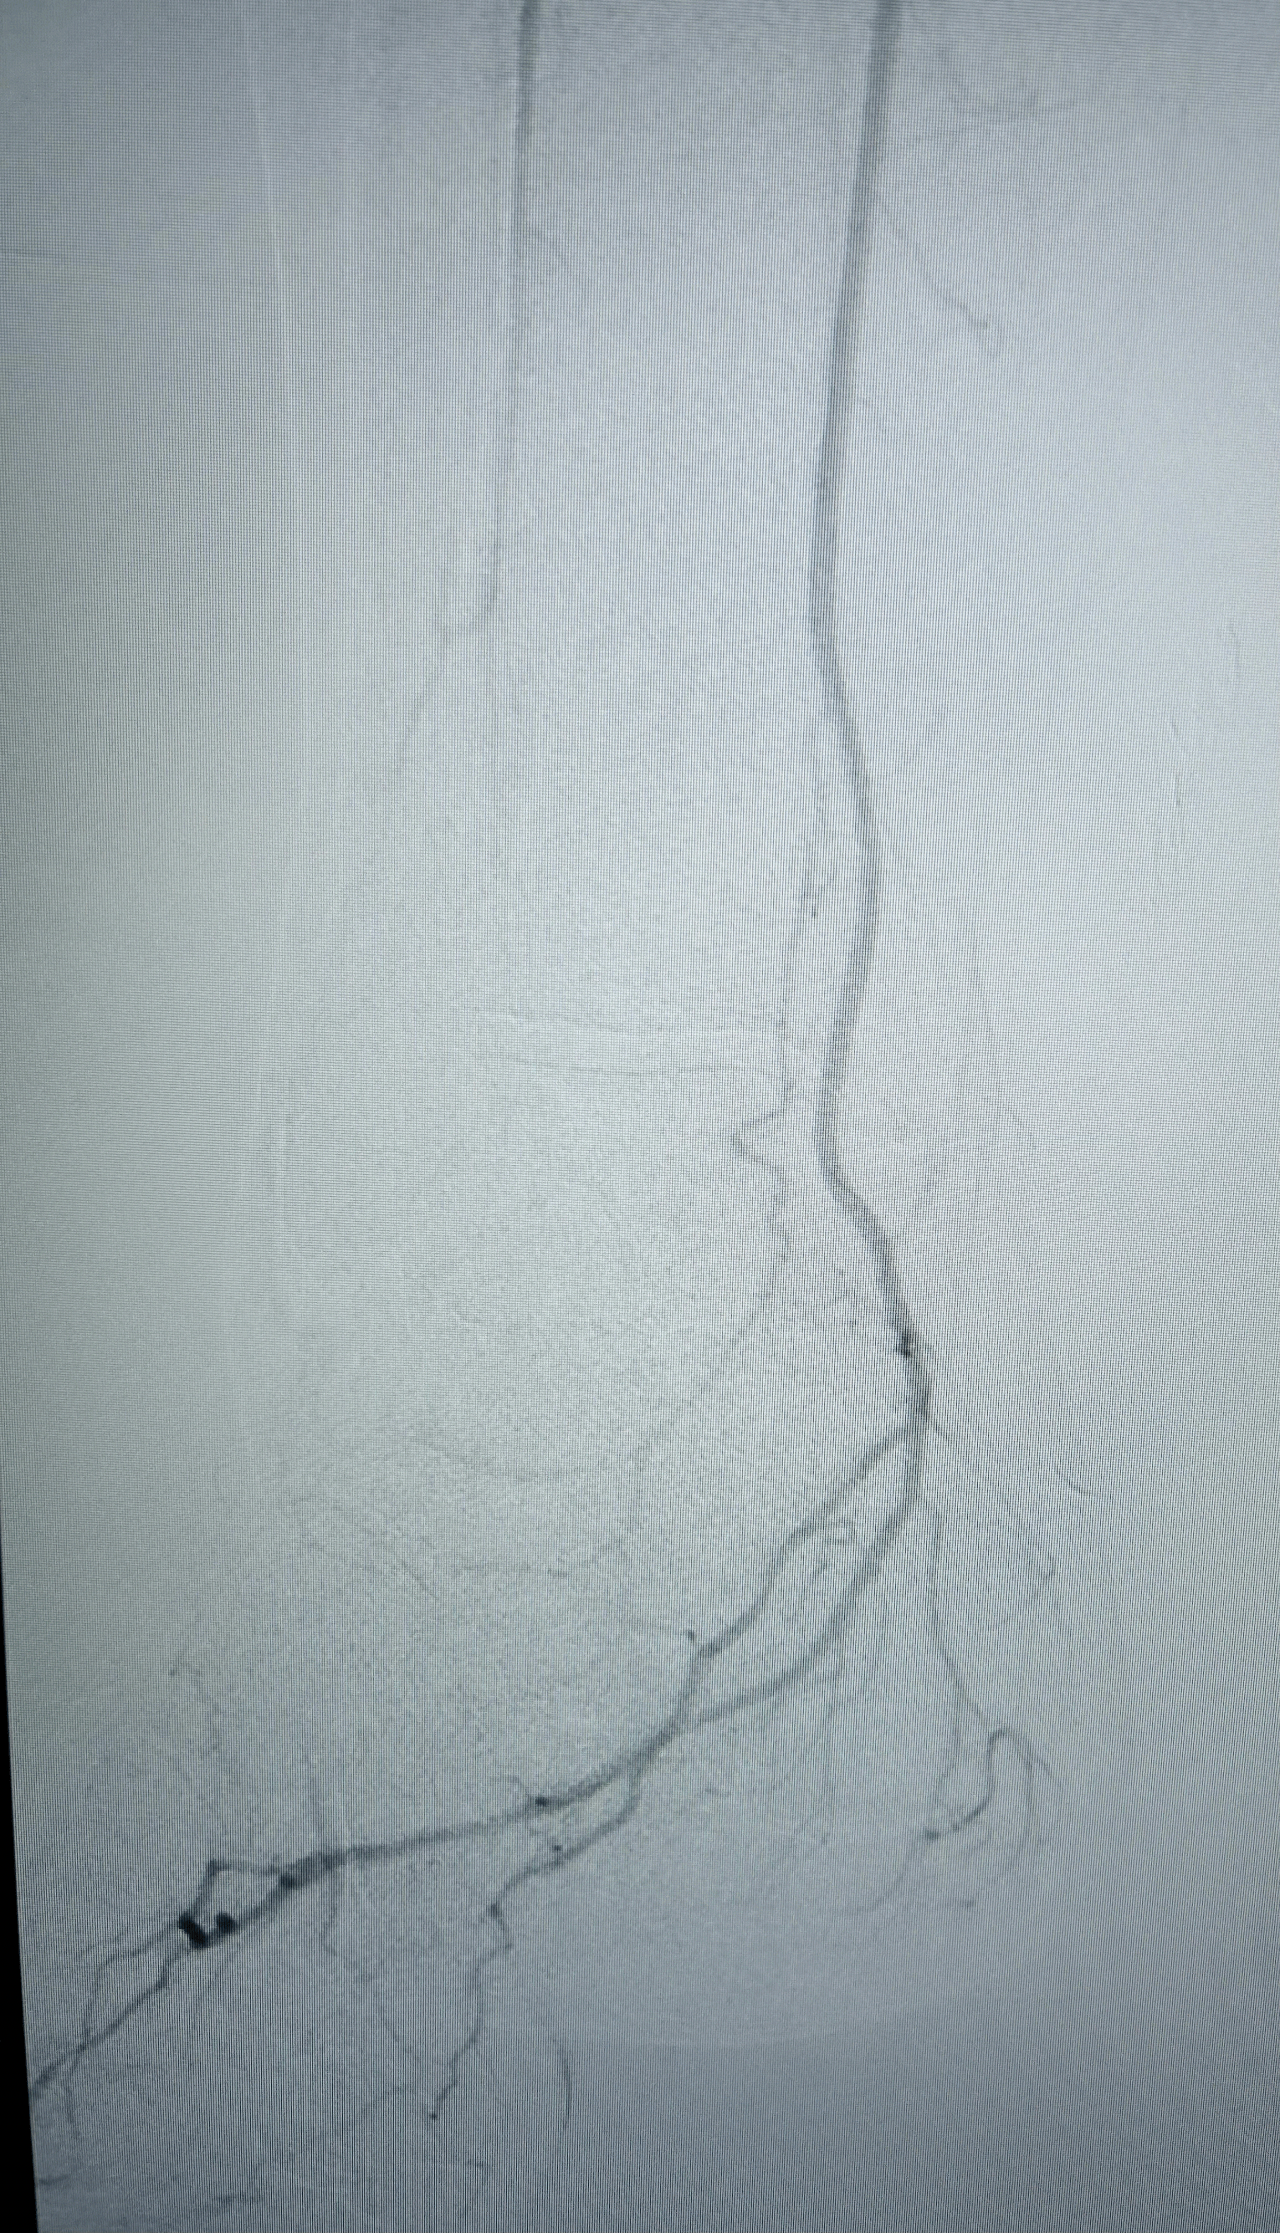

Résultat

Excellent résultat persistant de la recanalisation endoluminale des artères jambières sur le contrôle per-opératoire 15 min après la fin de la recanalisation.

Aucune embolisation distale constatée au niveau des artères du pied.

Disparition de l'ischémie du pied gauche.

Excellent pouls tibial postérieur gauche.

Image de spasme de l'artère tibiale postérieure en aval traitée par une injection intra-artérielle de 3mg de Risordan. Disparition immédiate du spasme.